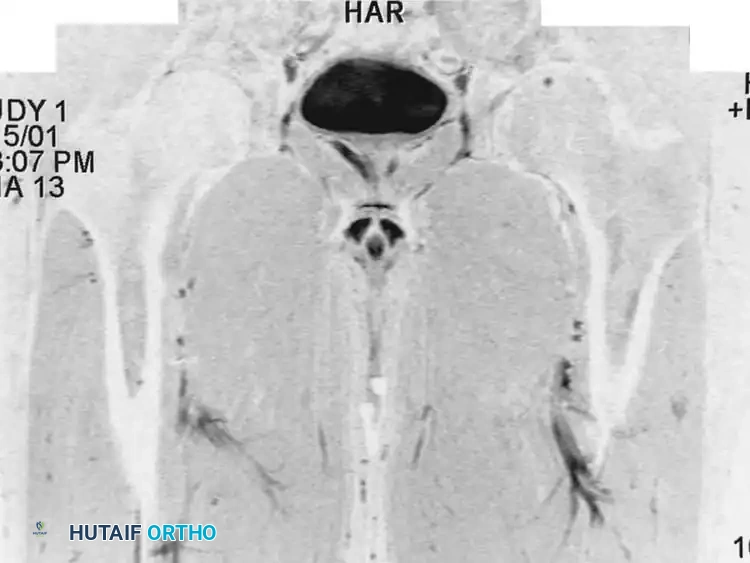

Fig. 20-21: Paget disease of the left proximal femur in a 45-year-old man. (A) Anteroposterior radiograph shows markedly coarsened trabeculae and cortical thickening. (B) Bone scan demonstrates intensely increased radiotracer uptake in the affected proximal femur.

Bone scintigraphy (Technetium-99m) is exquisitely sensitive, showing intensely "hot" lesions. Occasionally, the combination of aggressive plain radiographic features and a positive bone scan may mimic a primary bone sarcoma. In these instances, MRI is an invaluable diagnostic tool; despite the chaotic remodeling, the marrow signal in uncomplicated Paget disease typically remains normal (isointense to fat).